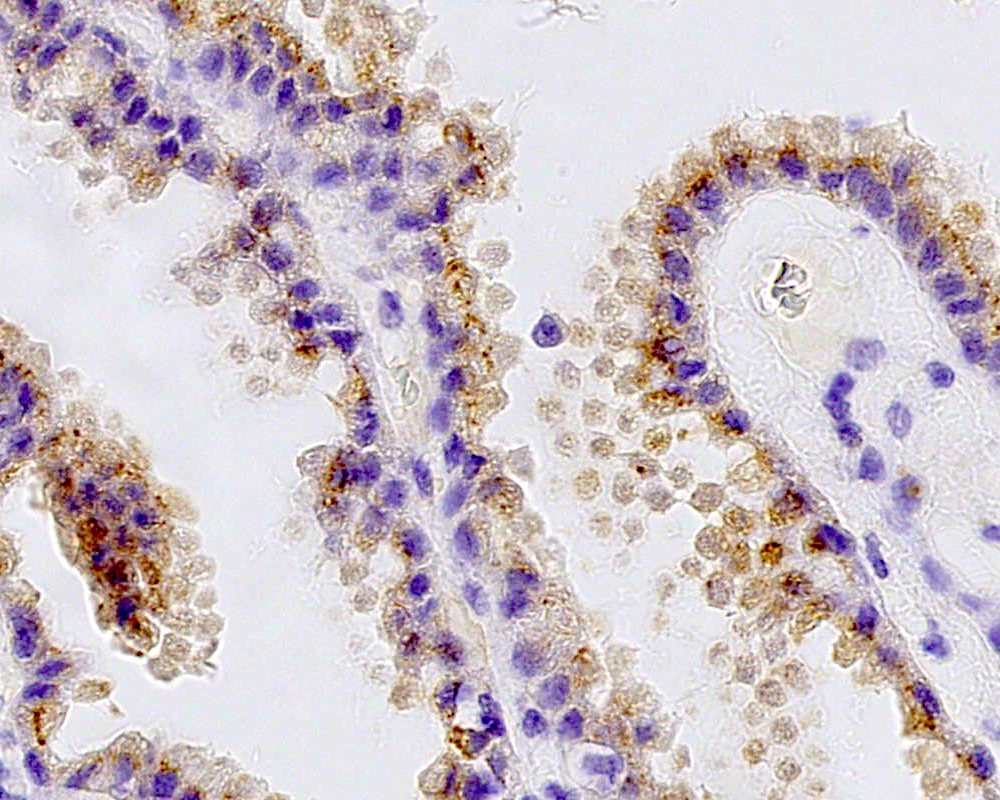

Microscopic (histologic) images

Positive stains

- Transthyretin, KIR7.1, EAAT1, S100, pancytokeratin (cytokeratin, MNF116, AE1 / AE3), CK7 > CK20

- Can be positive for GFAP, synaptophysin, S100

- Ki67 / MIB1 proliferation index may be used for grading (variable and subjective interpretation)

- Choroid plexus carcinoma: p53 variable, SMARCB1 / INI1 and SMARCA4 retained nuclear expression

- References: Neurosurgery 1988;23:384, Acta Neuropathol 1990;80:635, Am J Surg Pathol 2006;30:66, J Neuropathol Exp Neurol 1999;58:398